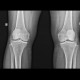

Selamat pagi sejawat, mohon bantuan arahan untuk kasus pasien wanita 64 tahun dengan keluhan lutut kanan bengkak dan nyeri jika berdiri lama, atau digunakan berjalan jauh.

Membaik saat istirahat dan menggunakan Cox-2 inihibitor.

dengan pembacaan radiologi: OA Lutut Kanan grade 3.